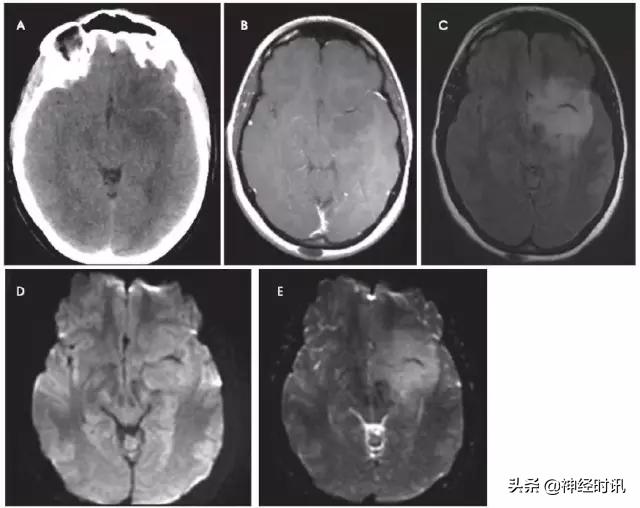

原发性脑肿瘤可以表现为急性神经功能缺损。有时低级别胶质瘤伴轻度水肿效应和皮层受累可能会与亚急性脑梗死混淆(图3),通过无血管分布、无明显弥散受限和脑沟强化,较易与其鉴别。但是,亚急性梗死伴出血和高级别出血性胶质瘤可表现为局部弥散受限、不同程度强化和占位效应,有时难以鉴别。

图3 一例49岁女性,突然醒来出现言语不清。最初CT报告左侧MCA区域脑梗死伴左侧MCA高密度(A),MRI显示非强化(B)、T2-FLAIR高信号(C)的膨胀性病灶伴弥散增加(D-DWI,E-ADC)。活检显示为间变性少突胶质细胞瘤。